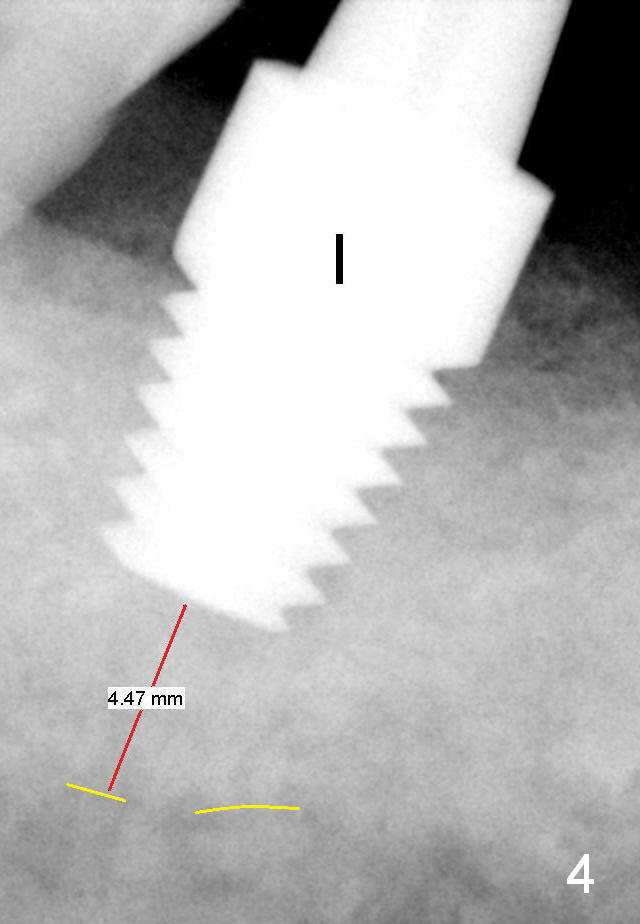

Following adjustment of trajectory (as compared to Fig.3), a 7x11 mm implant is placed with insertion torque 60 Ncm (Fig.4 I). Yellow dashed line: the upper border of the inferior alveolar canal.